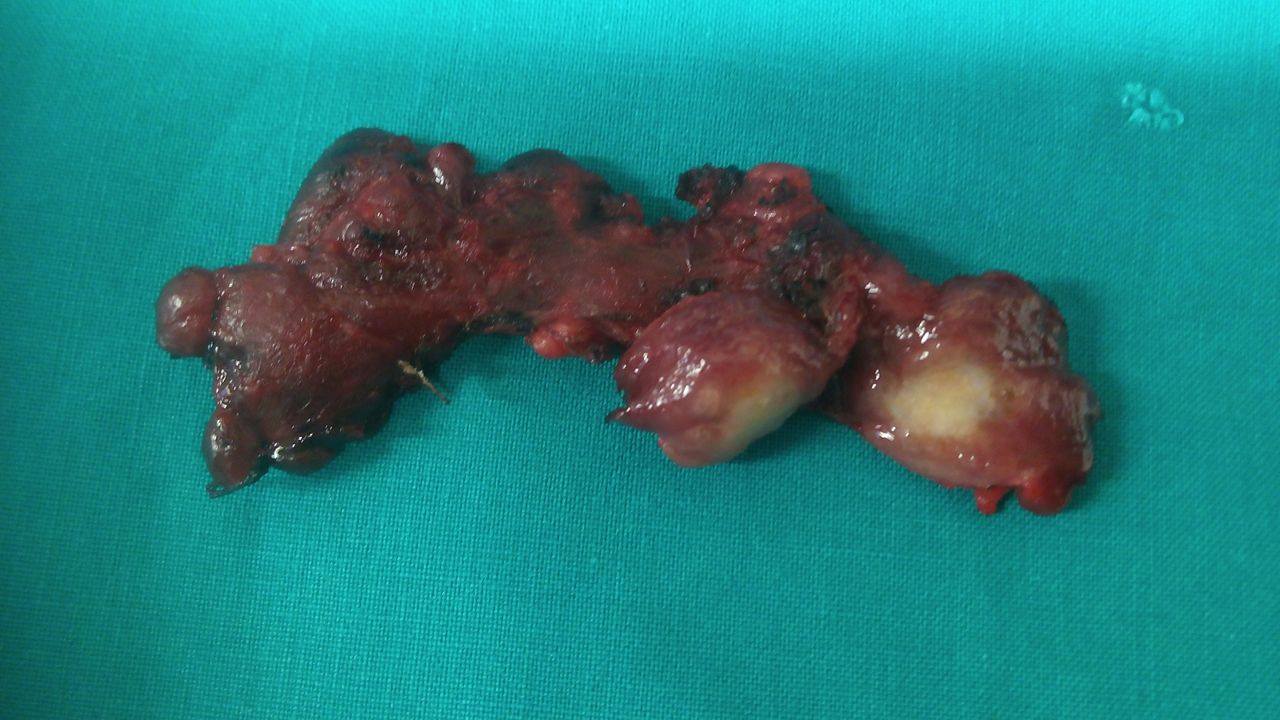

Figure 5 . Surgical specimen a) Blue arrows: encapsulated medullary microcarcinoma b) Yellow arrows : parathyroid glands . c) Green arrow : Benign thyroid nodule . ( Courtesy Dr . V . Penopoulos ) .